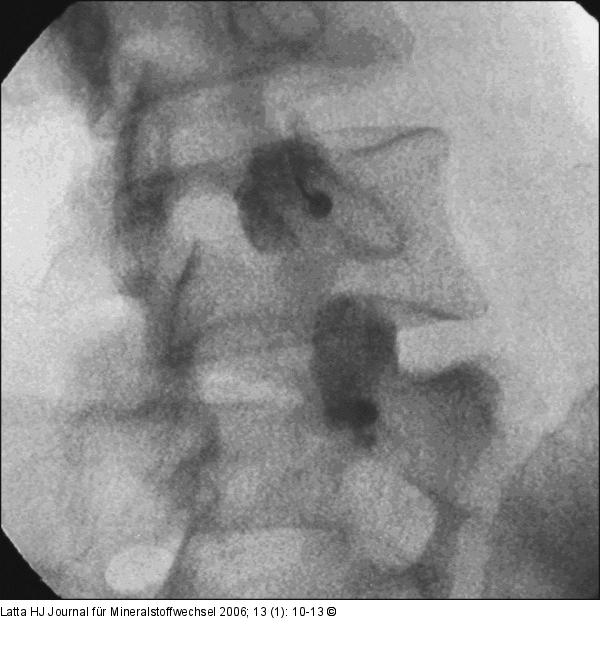

Abbildung 2b: Intraartikuläre Infiltration - Facettengelenk Intraartikuläre Infiltration der Facettengelenke L4/L5 u. L5/S1 rechts mit KM |

Abbildung 2b: Intraartikuläre Infiltration - Facettengelenk

Intraartikuläre Infiltration der Facettengelenke L4/L5 u. L5/S1 rechts mit KM |